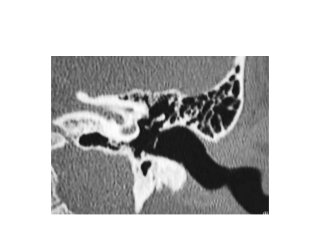

Subcochlear canaliculus type A

Subcochlear canaliculus type B

Subcochlear canaliculus type C

Temporal bone CT. Look at the sub-cochlear canaliculus or sub-cochlear

tunnel that can allow endoscopic transcanal retrocochlear access to the IAC

and drain the petrous apex cells